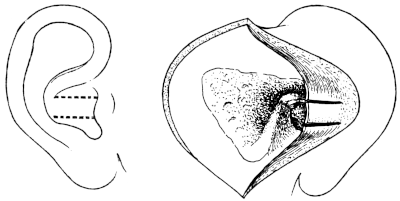

| 228. | Post-meatal Skin Flaps | 401 |

| 229. | Post-meatal Skin Flaps | 401 |

| 230. | Closure of Wound after ‘Radical’ Mastoid Operation | 401 |

| 231. | Körner’s Post-meatal Flap | 402 |

| 232. | Panse’s Post-meatal Flap | 402 |

| 233. | Stacke’s Post-meatal Flap | 402 |